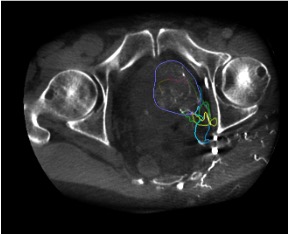

- Cone-beam CT (CBCT) is critical for identifying prostatic artery origins and mapping anastomoses before embolization

Pre-procedural CTA provides identification of prostatic artery origins in up to 97% of cases. However, intraprocedural cone-beam CT from the internal iliac artery remains essential for real-time confirmation of catheter position, identification of accessory prostatic branches, and assessment of dangerous anastomoses to bladder, rectum, and penile territories. The best angiographic projection to identify pelvic branches is the 20–50 degree ipsilateral oblique view with 10–20 degree caudal angulation.

CBCT Confirmation

CBCT Confirmation Landmarks

- Prostatic blush: diffuse parenchymal enhancement of the hemi-prostate on CBCT confirms correct catheter position — the defining landmark before embolization

- Central gland vs. peripheral zone: anteromedial branches supply the transition zone (BPH target); posterolateral branches supply the peripheral zone

- Foley catheter balloon (contrast-filled) helps identify bladder neck and prostatic urethra on CBCT

- 3D reconstruction models from proximal CBCT datasets allow advanced guidance for microcatheterization path planning

Non-Target Vessel Assessment

- Bladder branches: identified on CBCT as enhancement extending cephalad beyond the prostatic gland into the bladder wall. Caudal 10–20 degree view on DSA helps identify bladder branches

- Rectal branches: enhancement posterior to the prostate extending toward rectal wall — if identified, reposition microcatheter distal to branch origin or perform protective coiling

- Penile/pudendal branches: high-flow anastomoses to pudendal territory — protective embolization with coils or gelatin sponge may be needed